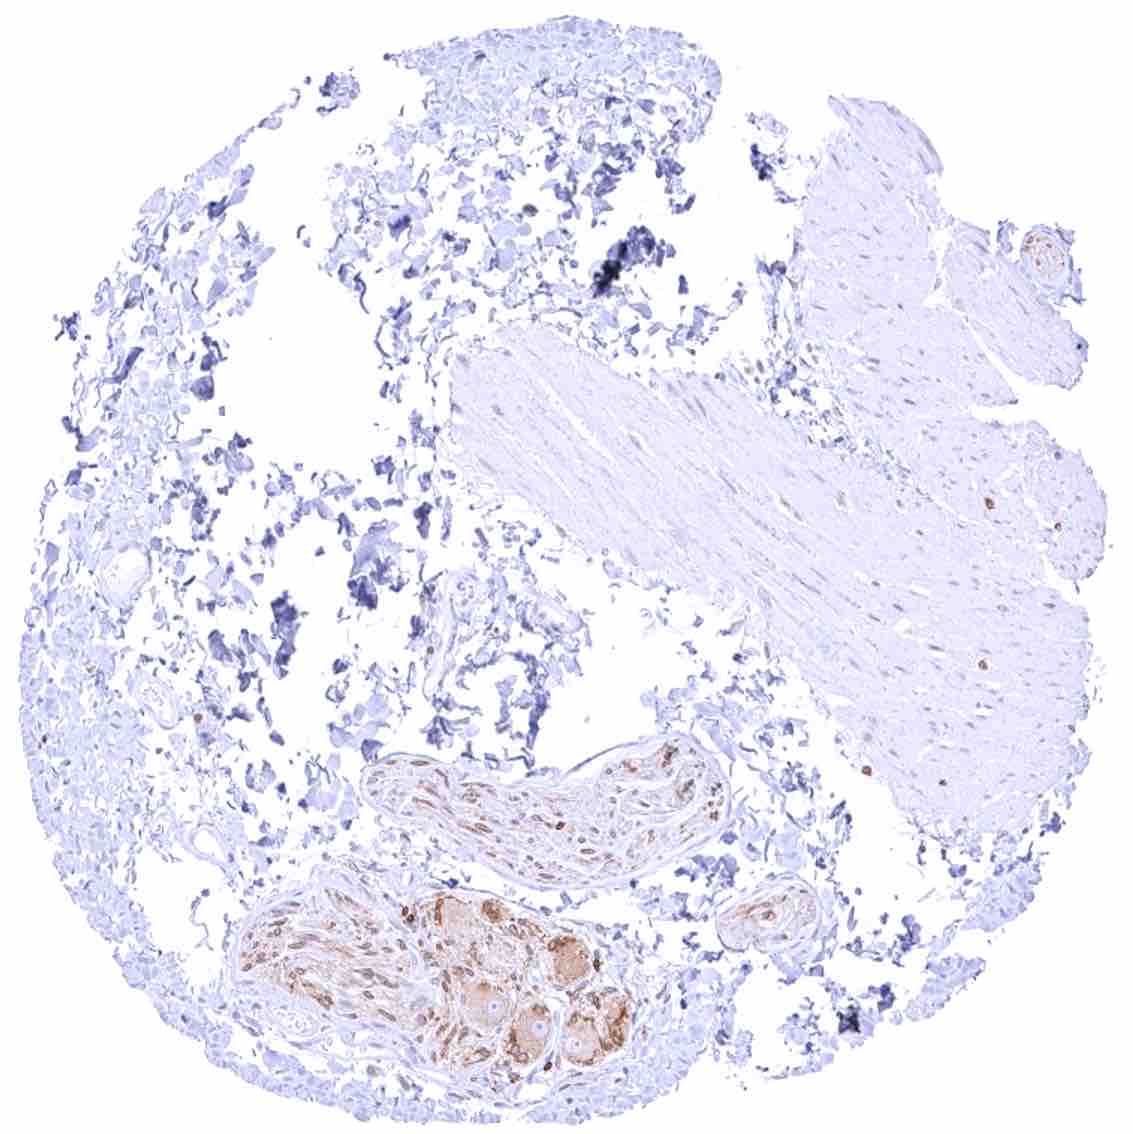

Lung – Pneumocytes are largely negative while a weak cytoplasmic bcl-2 staining can appear in some bronchiolar cells.